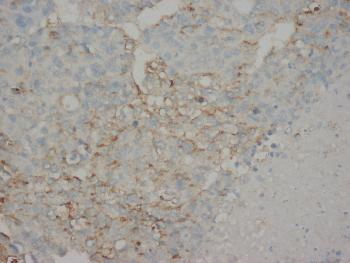

Figure 1: Immunohistochemistry of paraffin-embedded sections (kidney) Figure 1: Immunohistochemistry staining of human kidney (paraffin-embedded sections) with anti-cytokeratin 18 (C-04).

Immunohistochemistry (paraffin sections): Recommended dilution: 10 μg/ml; positive control: colon, kidney.

| Tissue Specificity: | Expressed in colon, placenta, liver and very weakly in exocervix. Increased expression observed in lymph nodes of breast carcinoma. |